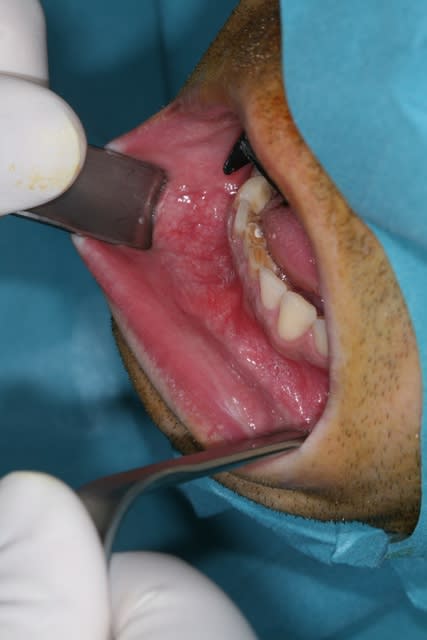

Non c'était un kyste d'origine dentaire à l'apex de 31 qui est lié à une nécrose après trauma 20 ans plus tot.

J'ai comblé avec du Pangen

C'est la situation clinique qui impose le tracé d'incision pas une loi universelle. En l'occurence j'aurais opté pour une incision dans la ligne muccogingivale (qui soit dit en passant est plus facile à réaliser car bien plus adaptée) si le kyste n'était pas aussi gros mais je ne suture pas sur du vide.

Sinon j'ai fait ça à la clinique sous AG et je suis orienté chir

Si bien entendu endo faite après séance CaOH à J-7 et obturation à J-2.